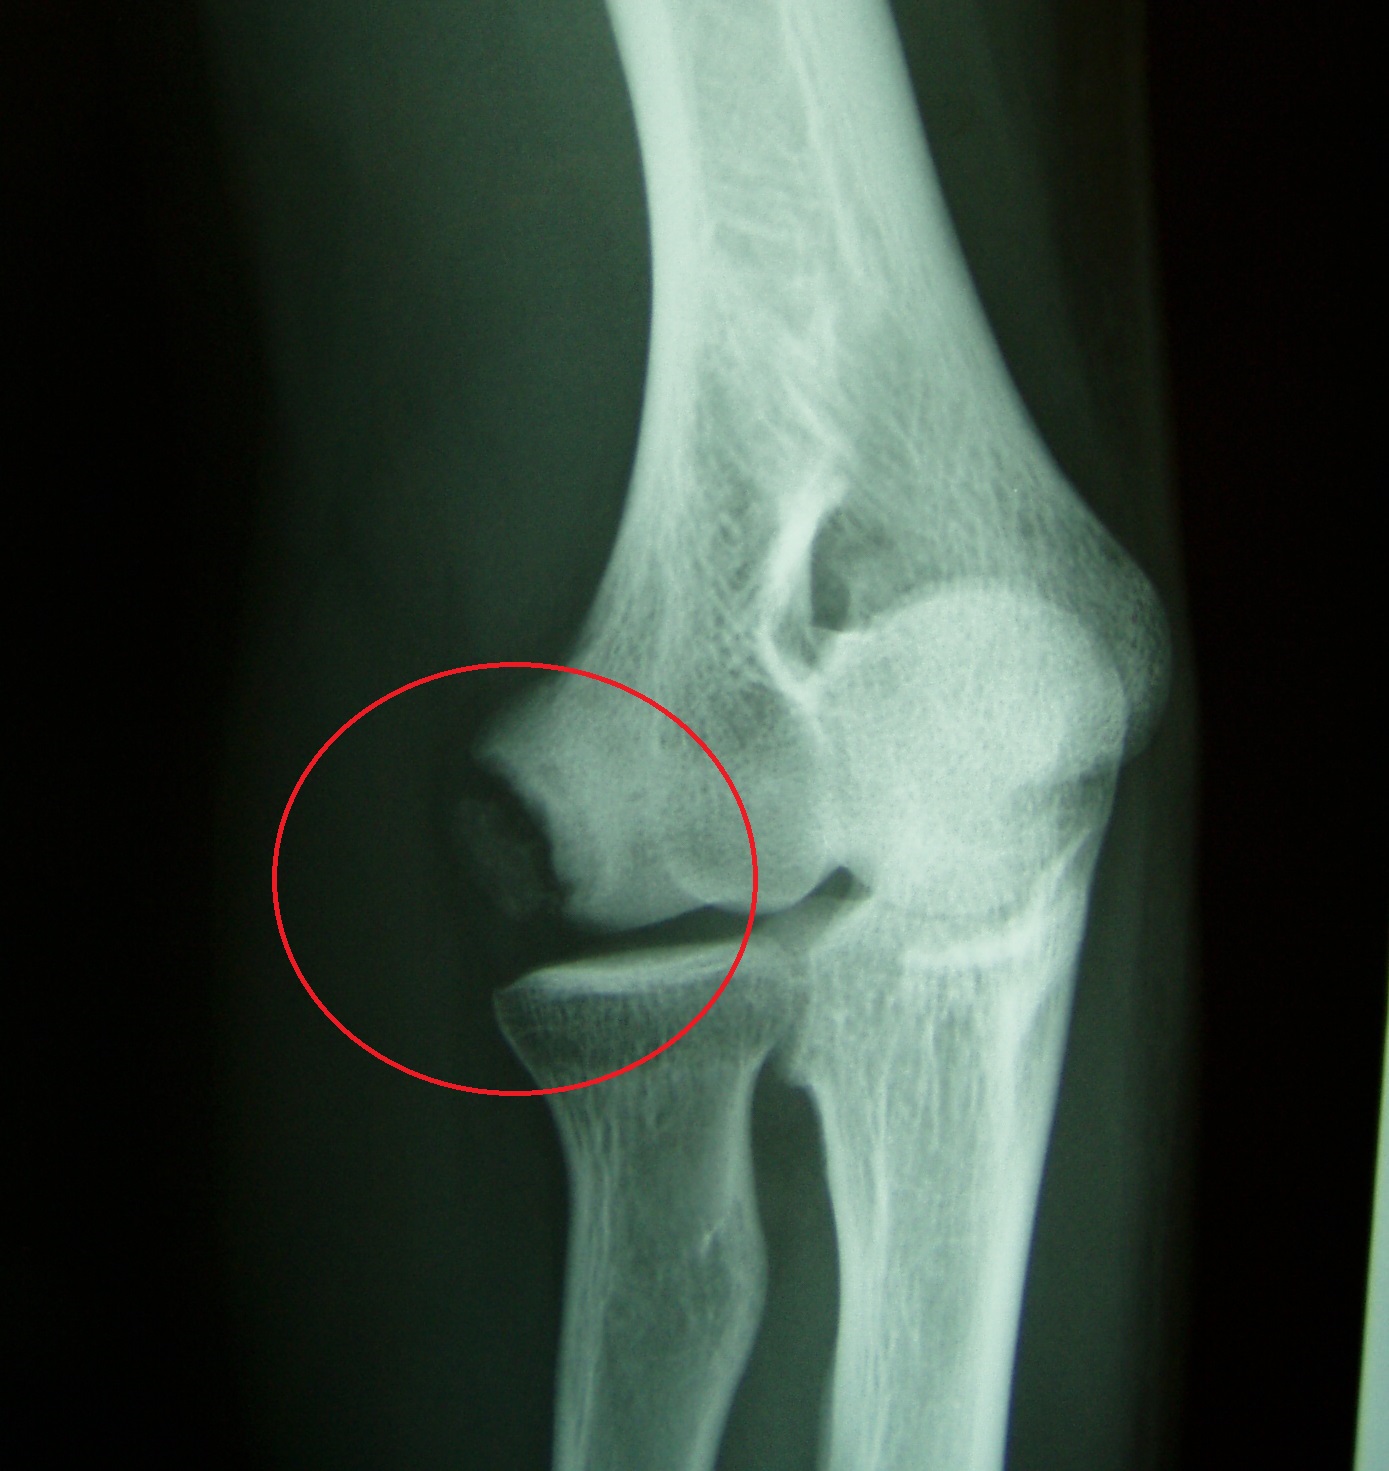

野球肘は名前のごとく、野球によるスローイング動作、特に成長期の投手に多く発生するオーバーユース(使いすぎ)に起因し、投球側の肘の①内側(図1)、②外側(写真1)、③肘頭(写真2)に発生する投球時の疼痛が主症状であるスポーツ障害です。徐々に発症する場合が多く、慢性化しやすいため肘の疼痛が出現したら注意を要します。投球動作の加速期(acceleration)は肘関節屈曲、外反、前腕回外位をとります。内側型は肘の内側部が投球動作時に回内屈曲筋によって牽引力が加わり、回内筋群や内側側副靱帯、尺骨神経がストレッチされ、内側に微細損傷が発生します。重症例では上腕骨内側上顆〈じょうか〉骨が牽引力によって剥離骨折を起こします。外側型は逆に肘外側にある上腕骨小頭や橈骨〈とうこつ〉頭に圧迫力が加わり、骨の壊死〈えし〉、欠損、遊離体などの離断性骨軟骨炎が発生します。後方型は減速期(follow-through)に肘伸展位で、尺骨肘頭に牽引力が加わり剥離や疲労骨折などの変化をきたします。

写真1 外側型:上腕骨小頭に骨遊離像を認める

上記症状に、レントゲンでの骨変化を認めます。内側型では上腕骨内側上顆の骨肥厚、骨端線離開、回内筋部への骨遊離像を、外側型では上腕骨小頭や橈骨頭の骨変形、欠損、遊離骨片の存在を、後方型では尺骨肘頭の亀裂骨折、疲労骨折像を認めます。